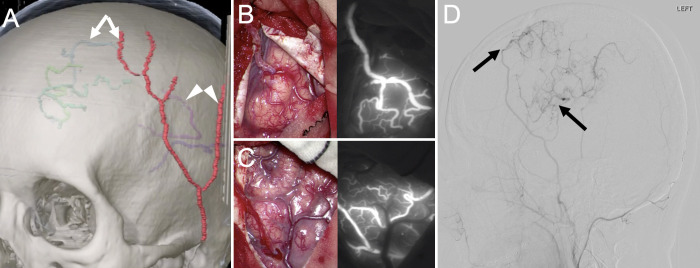

FIG. 3.

A: Preoperatively, the left STA parietal branch and left MCA (white arrowheads), left STA frontal branch, and left ACA cortical segment (white arrows) were identified on 3-dimensional CT angiography, and navigation mapping was used to determine the craniotomy area based on the location of the actual vessels. B: A small craniotomy was performed for the STA-MCA bypass, and the STA parietal branch and MCA were anastomosed with end- to-side anastomosis (left), with the patency of both bypasses confirmed on indocyanine green videoangiography (right). C: The STA frontal branch was anastomosed to the ACA cortical segment in the same manner (left), with the patency of both bypasses confirmed on indocyanine green videoangiography (right). D: Left external carotid artery angiography, lateral view, on day 7 showed bilateral patency of the bypass (black arrows).